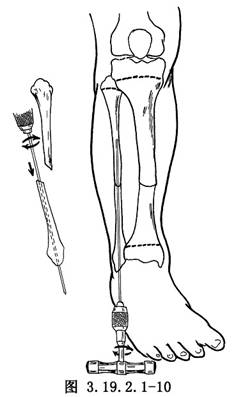

遊離骨端,切除遠、近端硬化的骨組織(圖3.19.2.1-7)。鑽通和擴大遠近端髓腔(圖3.19.2.1-8)。手法矯正脛骨向前成角畸形,並使健康的脛骨遠、近端互相嵌壓。有時需另做切口延長跟腱,以利脛骨成角畸形矯正。如腓骨完整使脛骨兩斷端分離,應另做切口,切除一段腓骨,才能使脛骨兩斷端對正(圖3.19.2.1-9)。以斯氏釘逆行法髓內固定切斷的腓骨(圖3.19.2.1-10)。這樣對脛骨的斷端也提供了良好的對位和固定作用。在手法矯正向前成角畸形時,最好使脛骨矯正到向後成角15°~20°(圖3.19.2.1-11)。

若脛骨遠端較長,可於脛骨遠端骺板上方1.25~2cm處和脛骨近側段橫行穿入斯氏針,用Charnley加壓器固定,保持脛骨兩斷端牢固嵌壓和良好對位(圖3.19.2.1-14)。若脛骨遠端短小,可用較粗的斯氏釘逆行法髓內固定脛骨。先從脛骨遠斷端向遠側打入斯氏釘,穿過脛骨遠端骨骺中心、踝關節、距下關節,從跟骨蹠面穿出,然後對正脛骨遠、近端,將斯氏釘打進脛骨近端,其理想的穿釘方向應使釘的近端恰在脛骨後側皮質。遠側釘尖埋於皮下(圖3.19.2.1-15)。